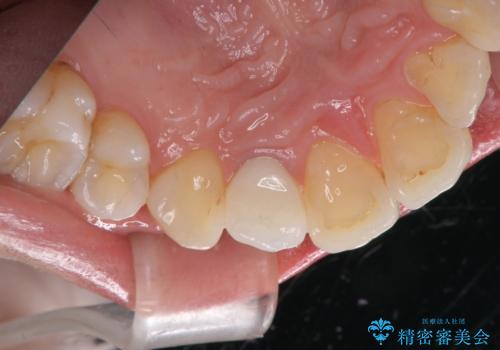

前歯の形と変色が気になる。 ジルコニアクラウンでの修復処置

- 右上前歯の形と色が気になるとのことで来院された患者様です。

残っている歯に亀裂が多く走っていたため、クラウンでの修復処置を行います。

歯ぐきの扱いに気を付けることで、術前よりも歯ぐきの位置が改善されました。